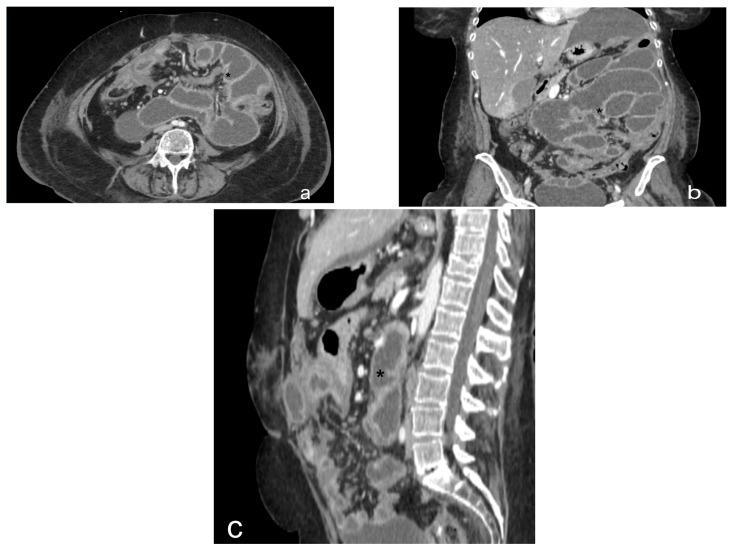

Peritoneal carcinosis is a condition characterized by the spread of cancer cells to the peritoneum, which is the thin membrane that lines the abdominal cavity. It is a serious condition that can result from many different types of cancer, including ovarian, colon, stomach, pancreatic, and appendix cancer. The diagnosis and quantification of lesions in peritoneal carcinosis are critical in the management of patients with the condition, and imaging plays a central role in this process. Radiologists play a vital role in the multidisciplinary management of patients with peritoneal carcinosis. They need to have a thorough understanding of the pathophysiology of the condition, the underlying neoplasms, and the typical imaging findings. In addition, they need to be aware of the differential diagnoses and the advantages and disadvantages of the various imaging methods available. Imaging plays a central role in the diagnosis and quantification of lesions, and radiologists play a critical role in this process. Ultrasound, computed tomography, magnetic resonance, and PET/CT scans are used to diagnose peritoneal carcinosis. Each imaging procedure has advantages and disadvantages, and particular imaging techniques are recommended based on patient conditions. Our aim is to provide knowledge to radiologists regarding appropriate techniques, imaging findings, differential diagnoses, and treatment options. With the advent of AI in oncology, the future of precision medicine appears promising, and the interconnection between structured reporting and AI is likely to improve diagnostic accuracy and treatment outcomes for patients with peritoneal carcinosis.

腹膜癌是一种以癌细胞扩散至腹膜为特征的病症,腹膜是衬于腹腔的一层薄膜。它是一种严重的病症,可由多种不同类型的癌症引发,包括卵巢癌、结肠癌、胃癌、胰腺癌和阑尾癌。腹膜癌中病变的诊断和定量对于该病症患者的管理至关重要,而影像学在这一过程中发挥着核心作用。放射科医生在腹膜癌患者的多学科管理中起着至关重要的作用。他们需要对该病症的病理生理学、潜在肿瘤以及典型的影像学表现有透彻的了解。此外,他们需要知晓鉴别诊断以及各种可用影像学方法的优缺点。影像学在病变的诊断和定量中起着核心作用,放射科医生在这一过程中起着关键作用。超声、计算机断层扫描、磁共振成像和正电子发射断层显像/计算机断层扫描(PET/CT)用于诊断腹膜癌。每种成像检查都有其优缺点,会根据患者情况推荐特定的成像技术。我们的目的是向放射科医生提供有关合适技术、影像学表现、鉴别诊断和治疗方案的知识。随着人工智能在肿瘤学中的出现,精准医学的未来似乎很有前景,结构化报告与人工智能之间的相互联系可能会提高腹膜癌患者的诊断准确性和治疗效果。